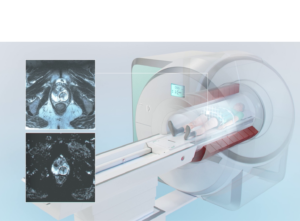

The diagnosis of prostate cancer involves several steps to determine the presence of cancer in the prostate gland and its aggressiveness. Abnormal prostate-specific antigen (PSA) blood test and digital rectal examination (DRE) are followed by either biopsy and/or a diagnostic MRI with PI-RADS scoring. Persistent suspicious cases require MR-guided targeted biopsy to establish diagnosis and the true aggressiveness of the tumor to determine the correct treatment.

A fusion prostate biopsy, also known as MRI-ultrasound fusion biopsy, is a diagnostic procedure used to target a cancer suspicious lesion within the prostate gland by fusing MRI diagnostic images with ultrasound guidance.

In-bore MR-guided biopsy is the most advanced diagnostic procedure using real-time MR imaging to target tumor suspicious lesions within the prostate gland and obtain tissue samples. By using the most sensitive imaging method combined with remote controlled navigation this allows for the most accurate diagnosis of prostate cancer.